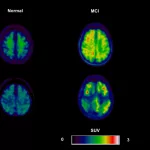

Most modern antidepressants focus on three key brain chemicals: serotonin, norepinephrine, and dopamine. By tweaking how these neurotransmitters are released, re‑absorbed, or broken down, the meds create a more “balanced” environment for mood regulation. For example, selective serotonin reuptake inhibitors (SSRIs) keep serotonin hanging around longer in the synapse, while serotonin‑norepinephrine reuptake inhibitors (SNRIs) do the same for both serotonin and norepinephrine.